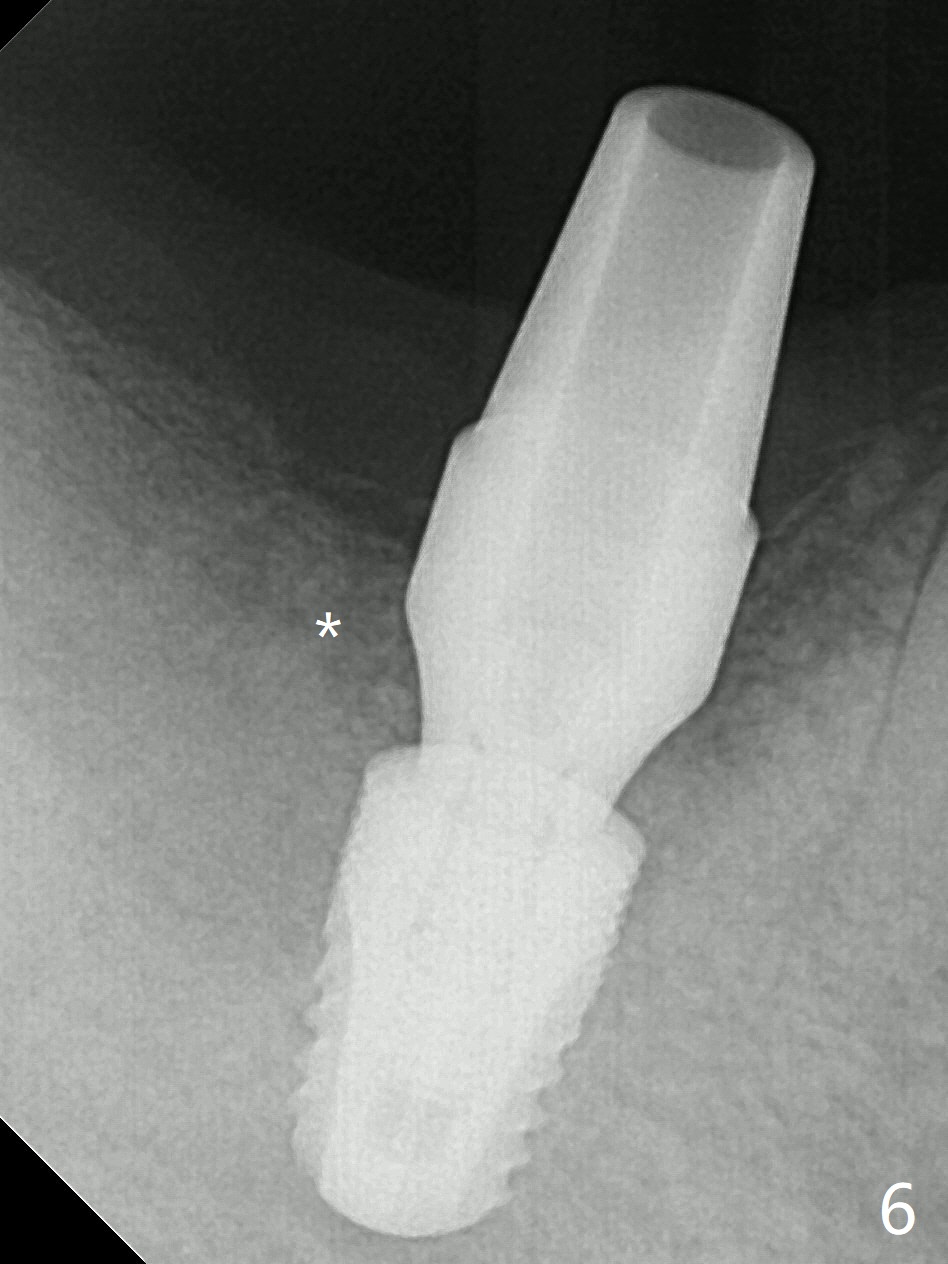

After extraction of the tooth #30, hemorrhage is excessive. With incision and buccal flap elevation, it is easy to remove residual granulation tissue and see the bony defect. With gauze pressure, hemostasis is manageable. Osteotomy is established in the mesial socket, i.e., mesial slope (Fig.1 yellow dashed line) with 2 mm initial drill from DIO Sinus Master Kit with 6 mm stop. After use of 3.8 and 3.6 mm round burs from the Master Kit for 6 mm, 4.1-5x8 mm drills from SM Kit are used with 50 RPM to control depth until the patient feels light pain with infiltration anesthesia. A 5.3 mm tap drill is inserted with 50 Ncm (Fig.2). A 5.3x8 mm SM implant is placed with >55 Ncm with clearance from the Inferior Alveolar Canal (Fig.3 red dashed line) with tightening a 5.8x7(6) mm abutment. The implant is subcrestal mesiolingually, equicrestal buccally and supracrestal distally (Fig.3 thread exposure distally between arrows). With Osteogen plug placed in the distal socket, allograft is placed around the implant and abutment (Fig.4 *). Periodontal dressing is applied following buccal placement of Collagen Dressing and suturing. The gingiva around the abutment is healthy 3.5 months postop; new bone appears to form distocoronal to the implant (Fig.5,6 *).